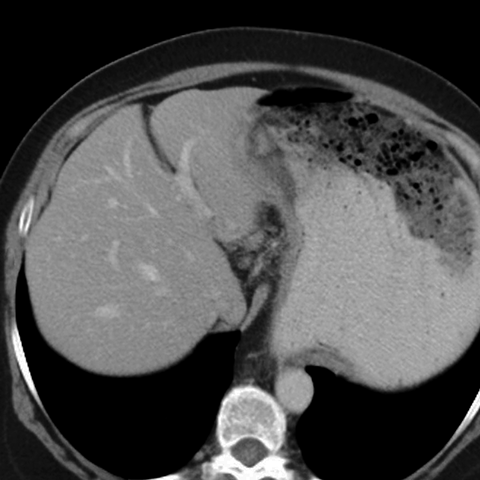

56 year-old male presents with abdominal pain and weight loss [2 of 5]